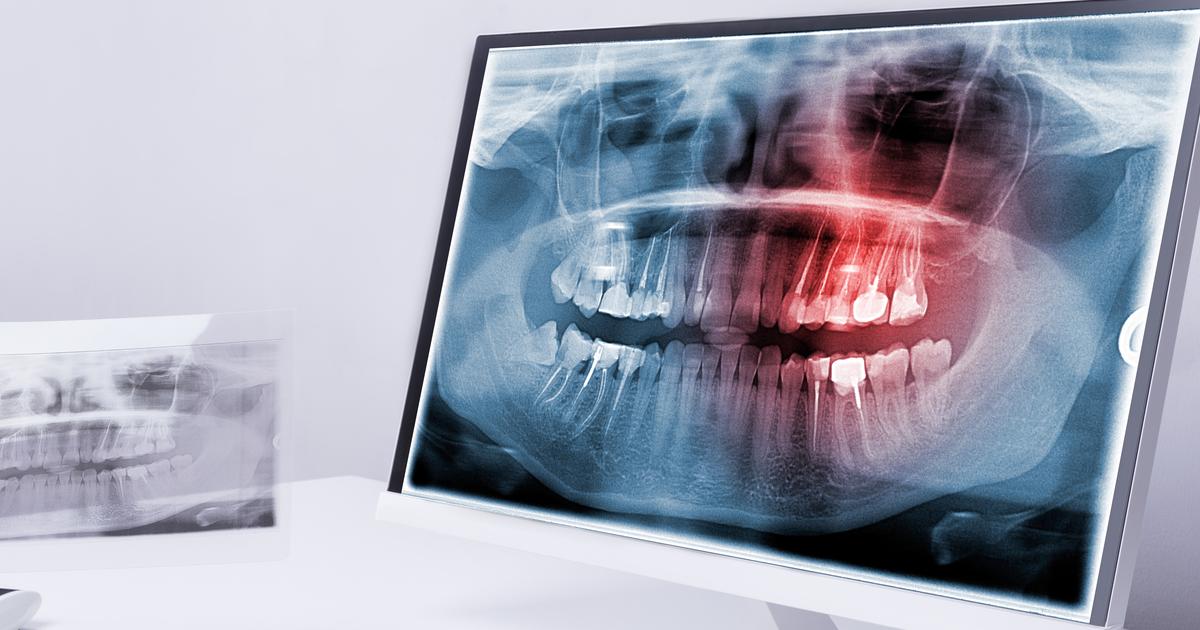

The placement of dental implants may put an individual at an increased risk of having bone loss in the years following the installation. Peri-implantitis is an infection that affects the soft tissue around the bone-integrated implant. The pathophysiology of this particular type of infection is known to be associated with a disruption in the equilibrium between an individual's defense system in the body and the microflora in their oral cavity. Plaque with microbial properties can form on the surface of an individual's dental implant the same way it can build up on the natural tooth surface. The soft tissues around the implant abutment become infected and inflamed due to the tissue's response to the bacterial presence. This infection can spread into the actual tissues of the bone itself around the implant fusion. Peri-implantitis often results in the breakdown of alveolar bone that surrounds the implant. It is estimated between ten and twenty percent of all patients who have a dental implant installed experience alveolar bone loss after the implant has been functional for about a decade. Bone loss following implant installation is technically defined by a bone loss of 1.5 millimeters as referenced on a radiograph within the first year or greater than 0.2 millimeters of bone loss for each subsequent year. Early treatment of this infection can prevent dental implant-associated bone loss.